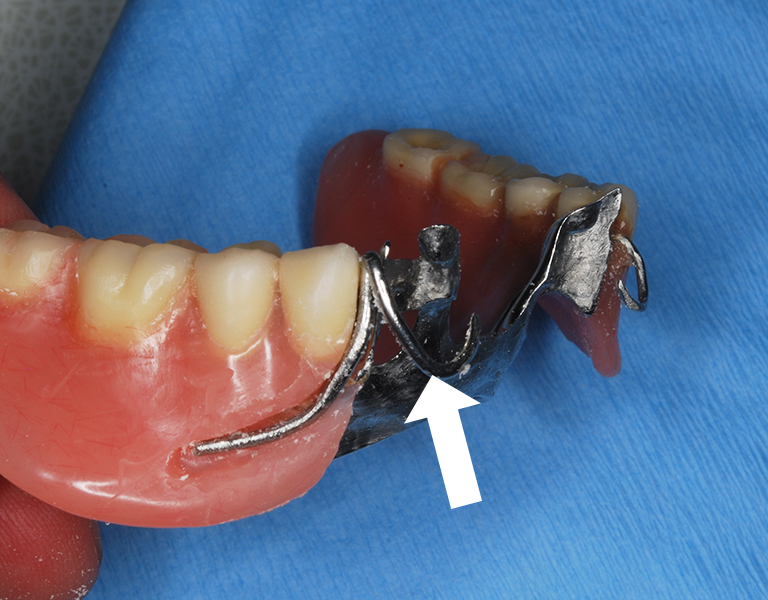

凹みの仮封鎖を取りクラスプ適合確認

義歯に組み込みレジンで固める

クラスプ修理の出来た義歯